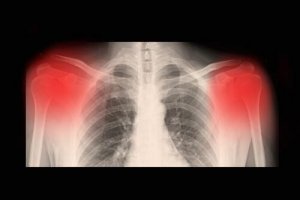

Vaak kan de diagnose plaatsvinden door middel van klinisch onderzoek. Normaal gesproken wordt dit gedaan via röntgenfoto’s, een CT-scan en/of een MRI-scan. Ook kan de mate van artrose vastgesteld worden door middel van een echo met hoge resolutie.